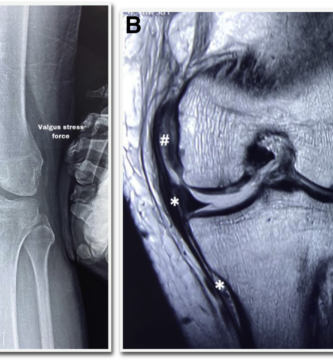

MCL TEAR CLASSIFICATION

SEVERE MCL INJURY

MODERATE MCL DAMAGE